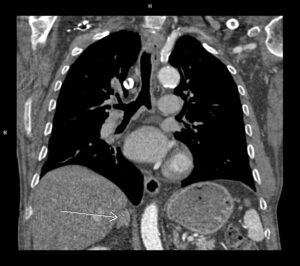

Figura 1: reconstrucție MIP cu diverticulul de origine a arterei subclavii stângi

Discuţie caz nr 130: examinare efectuată pentru suspiciune de dilatație anevrismală a aortei ascendente; achiziția a fost realizată cu sincronizare ECG pentru vizualizare optimă a valvei aortice și a peretelui aortic și surpriza a fost un arc aortic la dreapta cu aortă descendentă toracică la dreapta și o dilatație anevrismală / diverticul posterior de trahee și esofag și anterior de coloana vertebrală din care are origine arteră subclavie stânga (Diverticulul Kommerell).

DE LUAT ACASĂ!!! Achiziția cu sincronizare ECG la examinarea AngioCT aortă toracică este indicat / obligatoriu sa fie utilizată la pacienții care sunt trimiși la examinare CT pentru evaluarea aortei toracice. Diverticulul Kommerell se referă de obicei la configurația bulboasă a originii unei artere subclaviculare stângi aberante în contextul unui arc aortic drept. Cu toate acestea, a fost descrisă inițial ca o protuberanță diverticulară la originea unei artere subclaviculare drepte aberante cu un arc aortic stâng și se observă și în arterele vertebrale drepte aberante (arteria lusoria vertebrală).